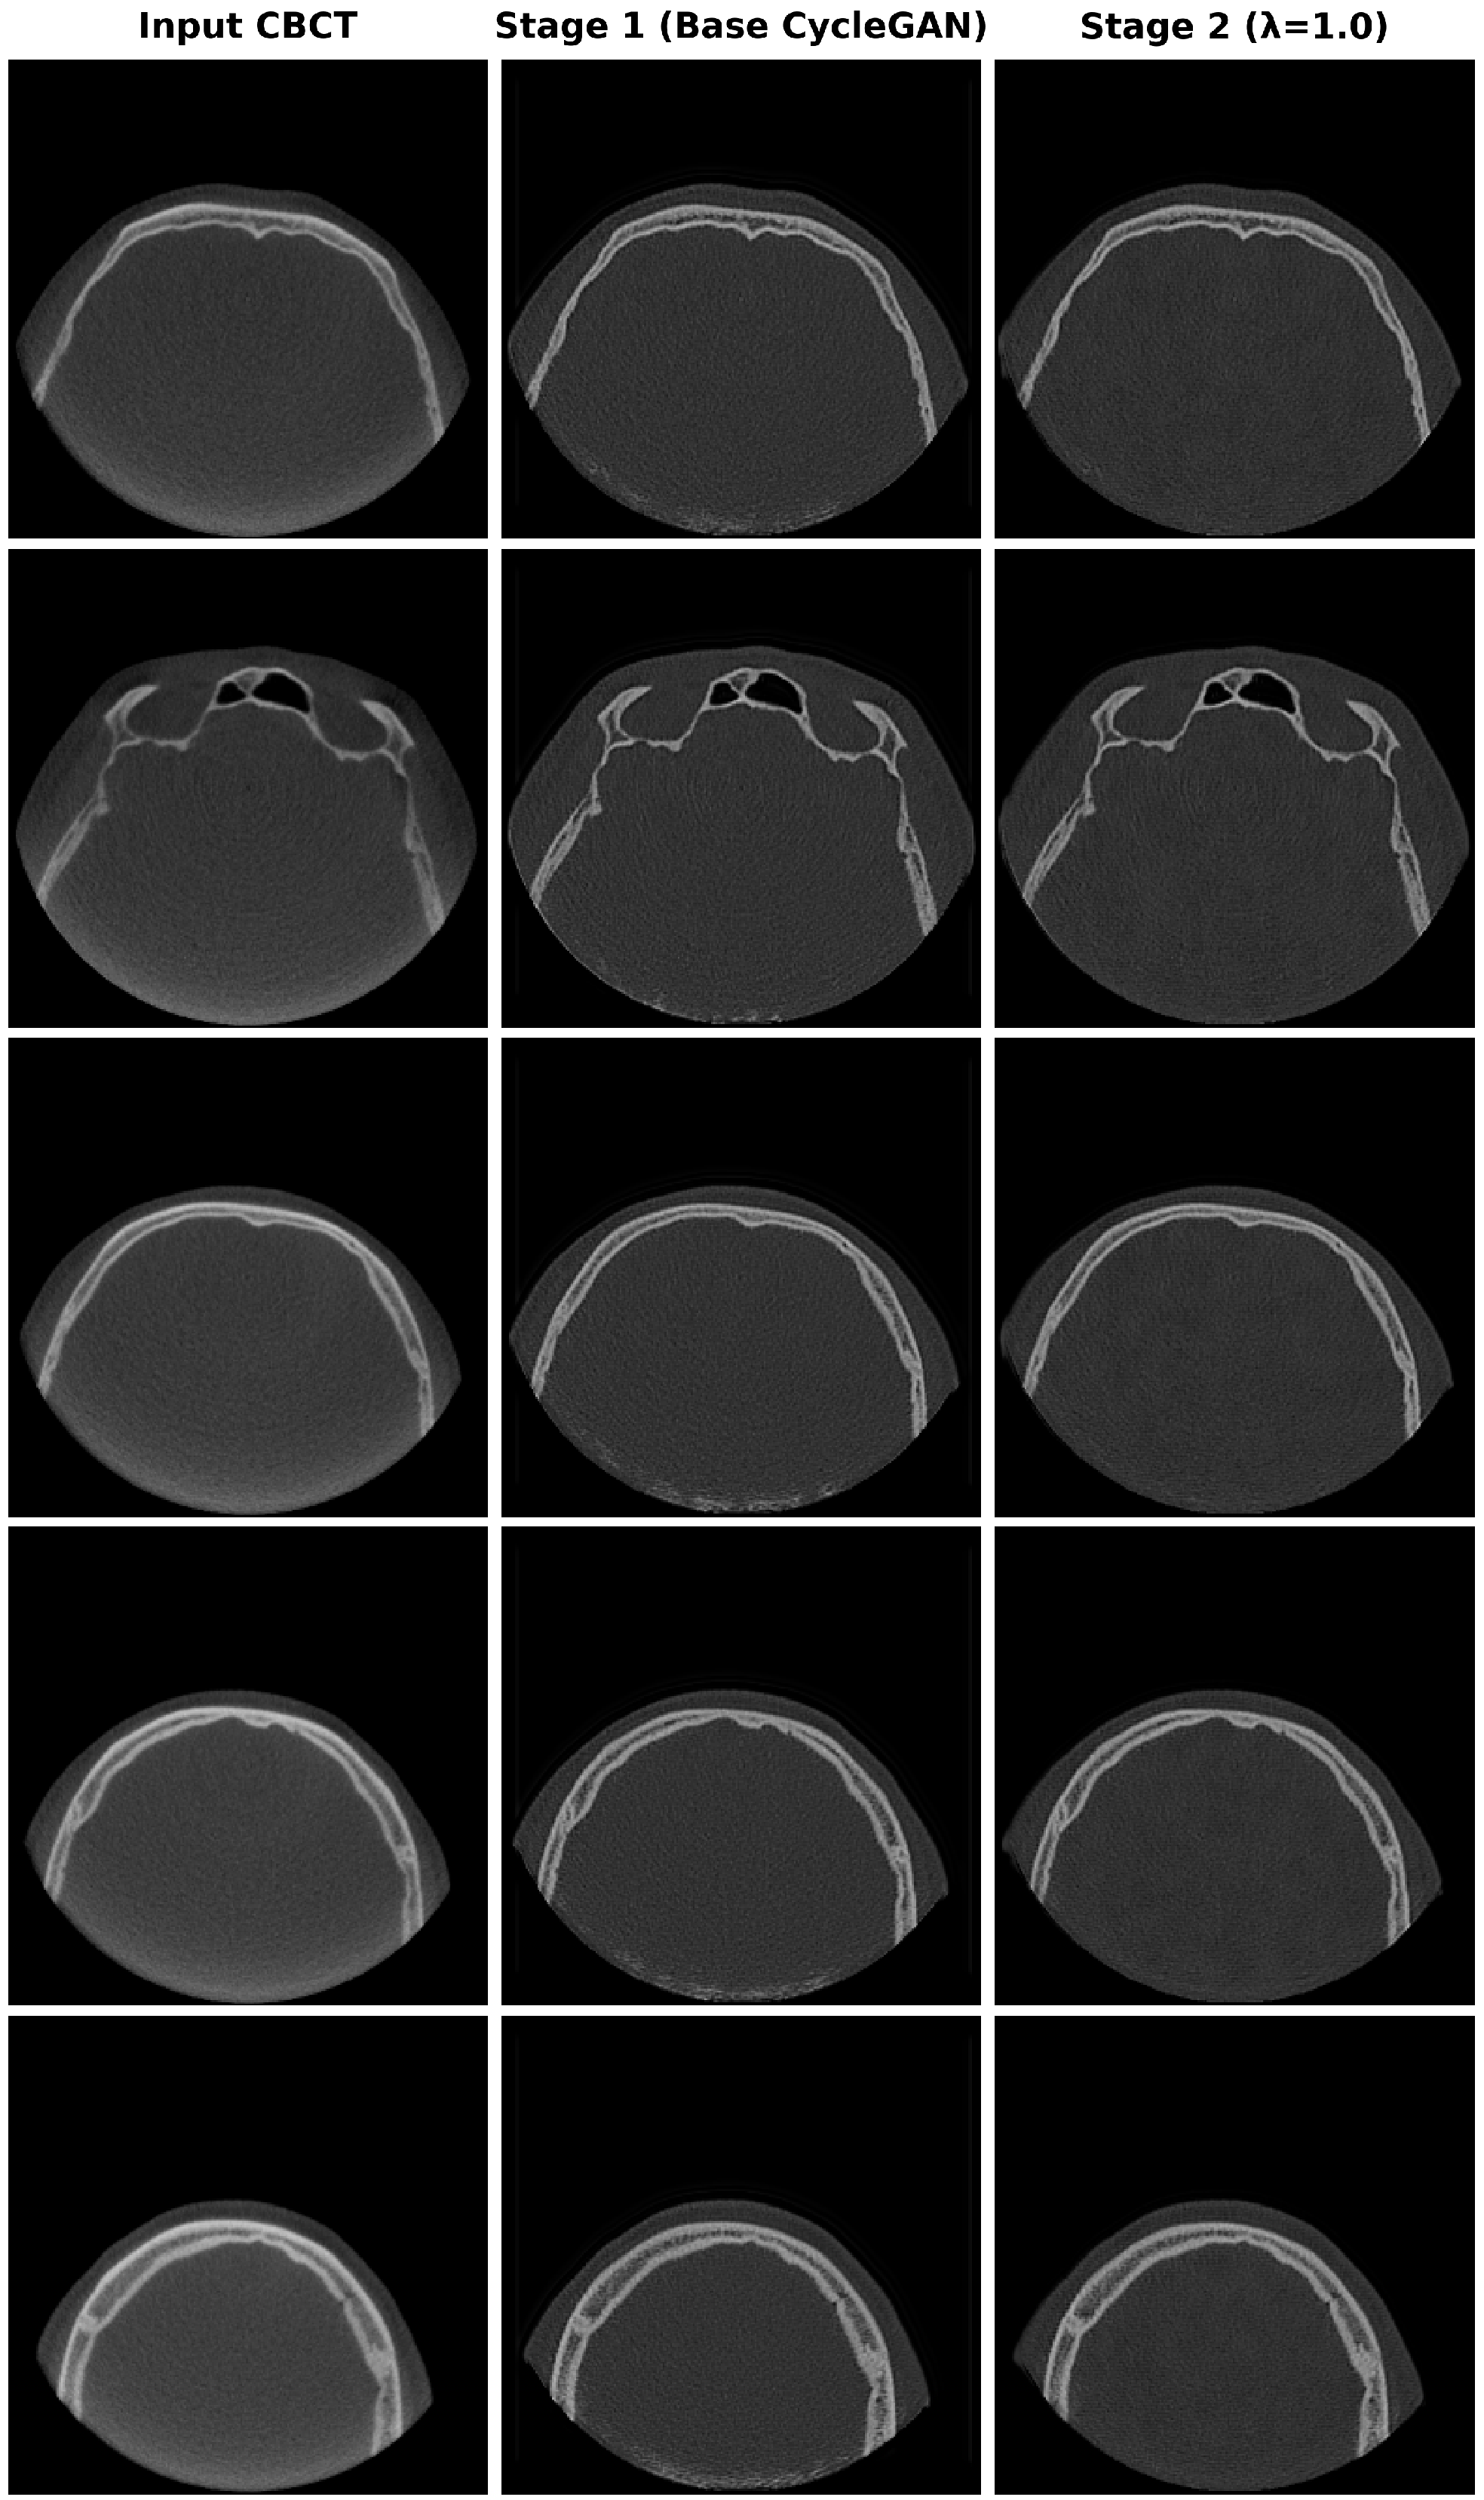

4.4. Qualitative Results